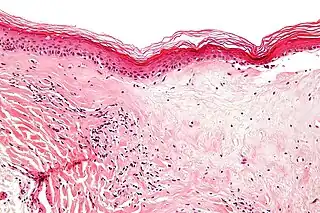

Microfotografía de liquen escleroso que muestra la esclerosis subepitelial característica (derecha/abajo de la imagen). Tinción hematoxilina-eosina.

Microfotografía del liquen escleroso extragenario: atrofia epidérmica, taponamiento folicular y vacuolización basal, y esclerosis con homogeneización inicial de colágeno en la dermis.[20]

Se puede hacer una biopsia de la piel afectada para confirmar el diagnóstico. Cuando se hace una biopsia, la hiperqueratosis, la epidermis atrófica, la esclerosis de la dermis y la actividad de los linfocitos en la dermis son hallazgos histológicos asociados con LS.[21] Las biopsias también se revisan para detectar signos de displasia.[22]